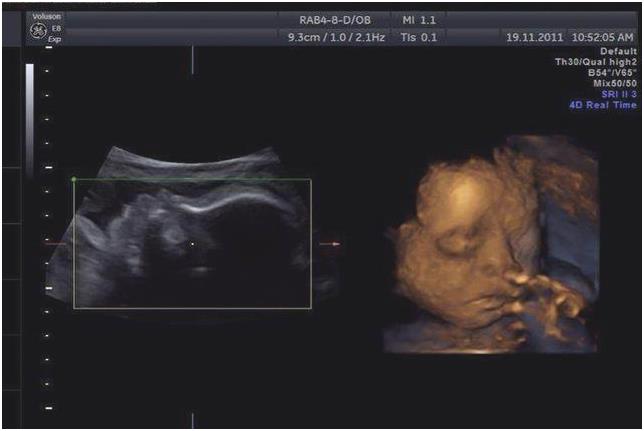

孕12周后,孕妈在医院进行建档,准妈妈们一定要按照医嘱按时产检,尤其是二胎妈妈们更应该积极产检,不要抱有侥幸心理。